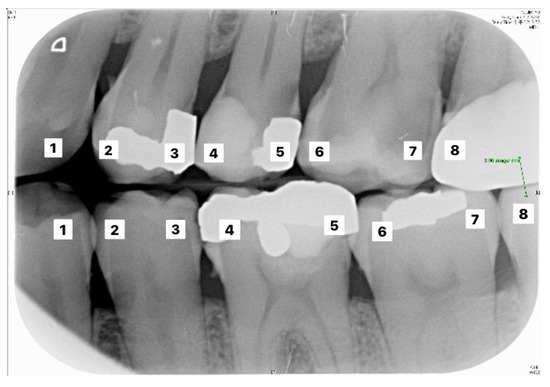

The validation set was used to evaluate the performance of the two established models. The actual number of findings in the photo with the predicted number of findings in the photo were compared to calculate the accuracy. The formula of accuracy is shown in Equation (7). Table 4 and Table 5 correspond to the execution results of the upper and lower teeth in Figure 9, respectively.

Figure 9.

Image example of outer teeth for validation (from left to right, in order of 1–8).

Table 6 and Table 7 correspond to the judgment of the upper and lower rows of teeth in Figure 10. Results show that the accuracy of the proposed model for judging the restorations was 95.56%, which is an improvement compared to Lin et al. [30], with an accuracy of 90.23%. The proposed method in Lin et al. [30] first enhanced the classification features of the image, and then added the regular term and impulse, before establishing a CNN model with the ReLU function. With regard to judging caries, the proposed model in this study showed an accuracy of 90.30%, which was also an improvement compared to Singh and Sehgal [31], with an accuracy of 80.00%, which used a neural network classifier to classify caries. Table 8 and Table 9 are the truth tables of different CNN models.

Figure 10.